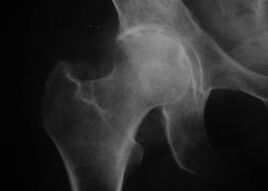

Appearance of the joint in arthrosis

Coxathrosis, hip joint arthrosis

With this disease, the classic clinical picture of arthrosis can be observed.

The first symptom of coxarthrosis is discomfort in the hip joint after physical activity.

In case of progressive coxarthrosis, the pain increases, stiffness and limited movement appear.

Patients with severe coxarthrosis spare the affected limb, avoid stepping on it, and choose a body position in which the pain is least noticeable when standing.